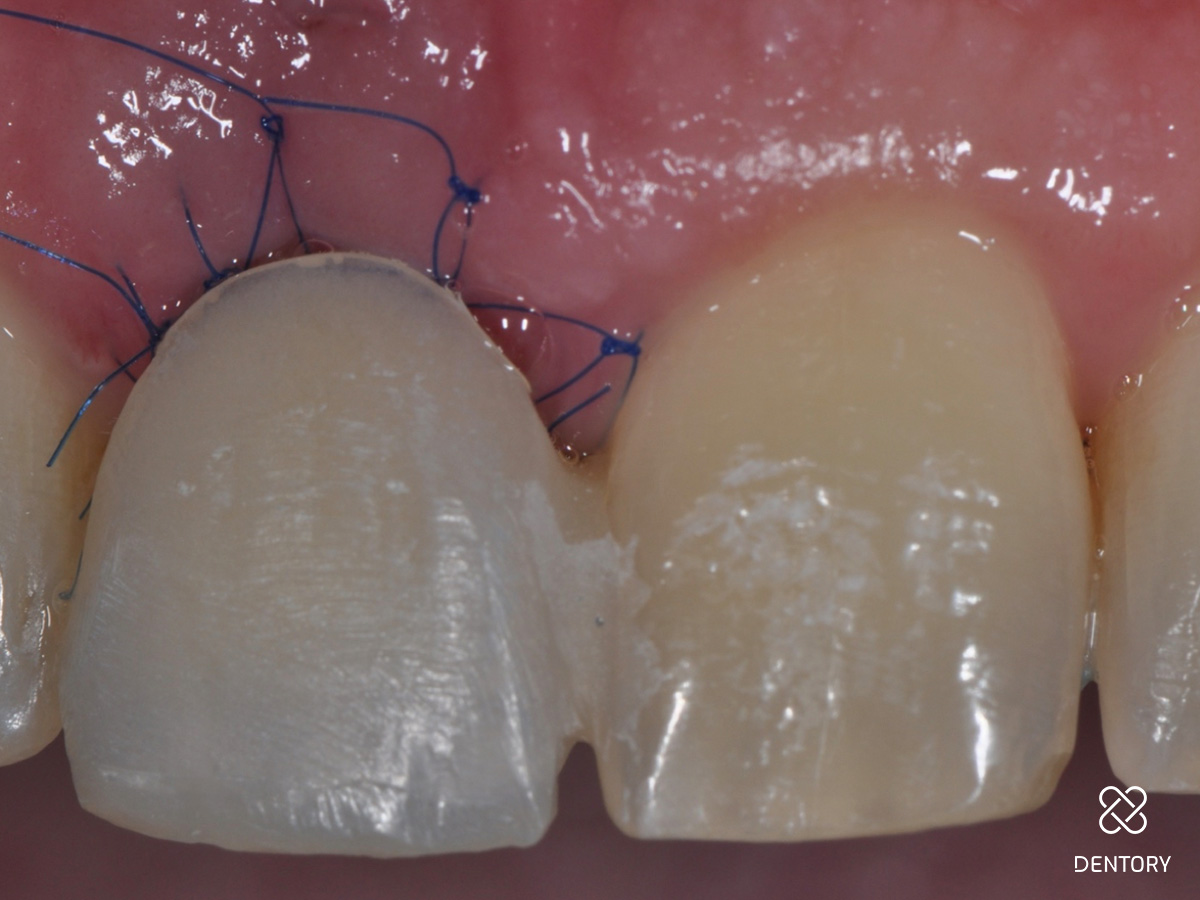

Abbildung 1

Ausgangssituation: Frontalansicht.